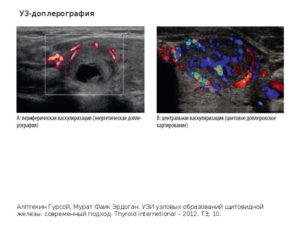

Возможность дифференциации доброкачественных и злокачественных образований яичников с помощью цветового допплеровского картирования (ЦДК) представляет собой перспективное направление в ультразвуковой диагностике.

Основным достижением ЦДК в диагностике опухолевых процессов является визуализация и оценка кровотока новообразованных сосудов опухоли, которые имеют свои характерные особенности. Система васкуляризации опухоли представлена множеством мелких, очень тонких, аномальных по форме и расположению сосудов, хаотично разбросанных в пределах опухолевых тканей.

Кровоток в этих сосудах характеризуется крайне низким сосудистым сопротивлением, высокой скоростью и разнообразным направлением.

Особенности кровотока обусловлены трансформацией кровеносных сосудов в широкие капилляры или синусоиды, лишенные гладкой мускулатуры, наличием прекапиллярных дренажей и множественных артериовенозных анастомозов с очень низким сосудистым сопротивлением, которые обеспечивают высокую кинетическую энергию кровотока и широкую вариабельность его направления.

По мнению большинства авторов периферическая, с единичными сосудами, васкуляризация опухоли должна ассоциироваться с доброкачественностью, а наличие множественных сосудов в центральной части, на перегородках и в папиллярных разрастаниях является признаком злокачественноcти.

- цветное допплеровское картирование (ЦДК);

[info name=”Для справки! “]ЦДК кровотока относится к ультразвуковым исследованиям, за счет методики выполнения дающее четкую картину состояния кровеносных сосудов с указанием направления притока и оттока крови. Кроме того, при ЦДК возможно выполнить и некоторые количественные замеры.[/info]

В таких случаях исследования посредством ЦДК становиться некоторым определителем признаков типа нарушения и может говорить о рисках озлокачествления присутствующего узла.

В зависимости от типа кровоснабжения измененной фолликулы, то есть перинодулярный или интранодулярный кровоток, можно говорить об определении рисков.

Узлами с интранодулярным типом кровоснабжения считаются те из них, которые обеспечены внутренним кровотоком, остальные следует относить к перинодулярным.